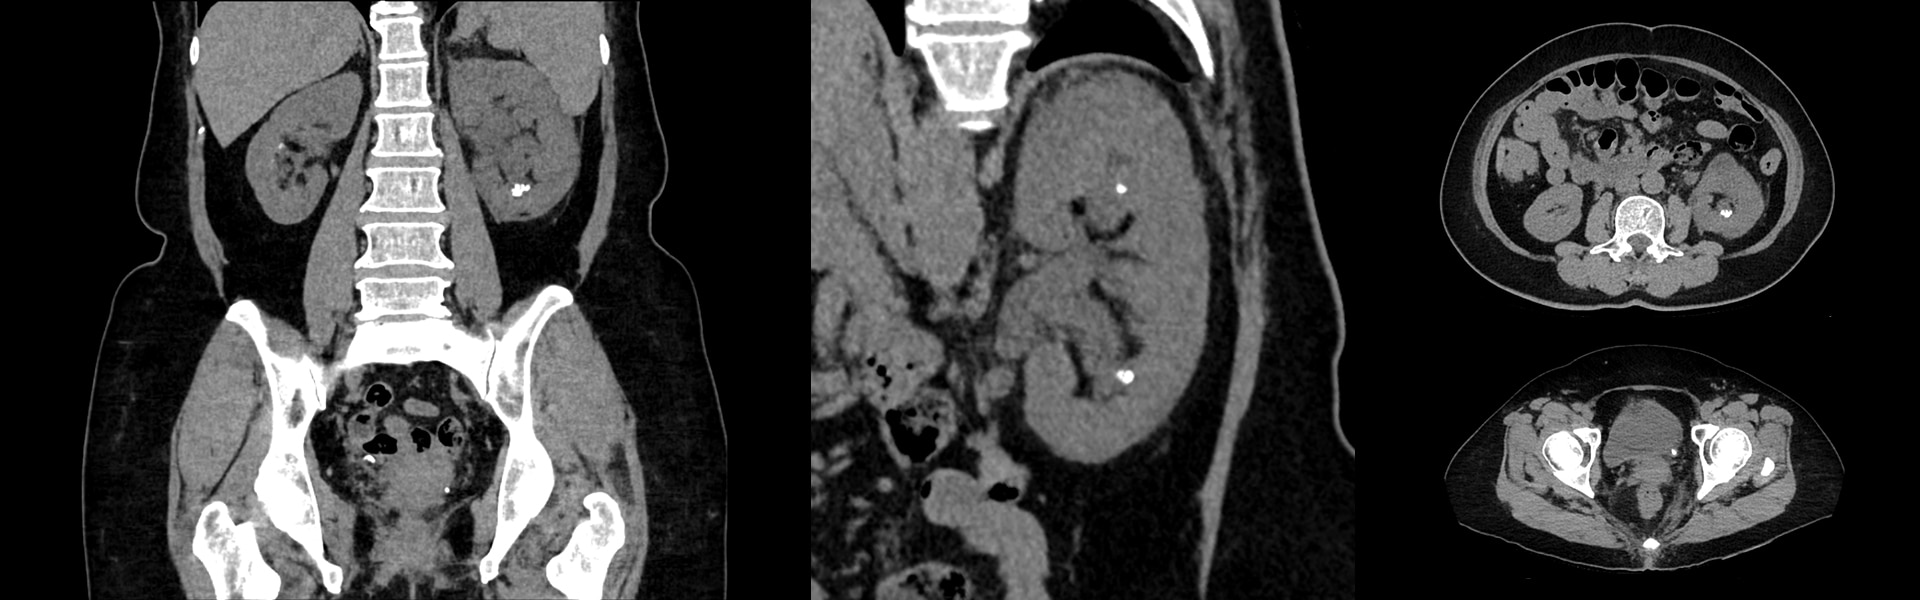

Images cliniques

Utilisation prévue : Le système Discovery MI Gen2 TEP/TDM est destiné à l’imagerie TEP corrigée de l’atténuation par TDM de la distribution des produits radiopharmaceutiques émetteurs de positrons anatomiquement localisée. Il est destiné à l’imagerie du corps entier, de la tête, du cœur, du cerveau, du poumon, du sein, de l’os, des systèmes gastro-intestinal et lymphatique, et d'autres Le système est également destiné à l'imagerie tomodensitométrique diagnostique (CT).

Le système est conçu pour produire des images en coupe du corps par reconstruction informatique des données de transmission des rayons X prises sous différents angles et selon différents plans, y compris les acquisitions axiales, ciné, hélicoïdales (volumétriques), cardiaques et synchronisées. Ces images peuvent être obtenues avec ou sans produit de contraste. Ce système peut inclure l’analyse des signaux et l’équipement d’affichage, les supports de l’équipement et du patient, les composants, et les accessoires. Il peut également inclure le traitement de données et d’images pour produire des images dans différents plans transaxiaux et reformatés. Les images peuvent être ensuite post-traitées pour produire des plans d’imagerie ou des résultats d’analyse supplémentaires. Le système est destiné aux applications de tomographie à rayons X de la tête, du corps entier, du coeur et du système vasculaire chez des patients de tous âges. Ces résultats sont précieux pour le diagnostic des maladies, traumatismes ou anomalies, ainsi que pour la planification, les indications et le suivi thérapeutiques - Classe : IIb - Fabricant : GE Healthcare Japan Corporation - Représentant : GE Medical Systems SCS - Buc-GMED #37618